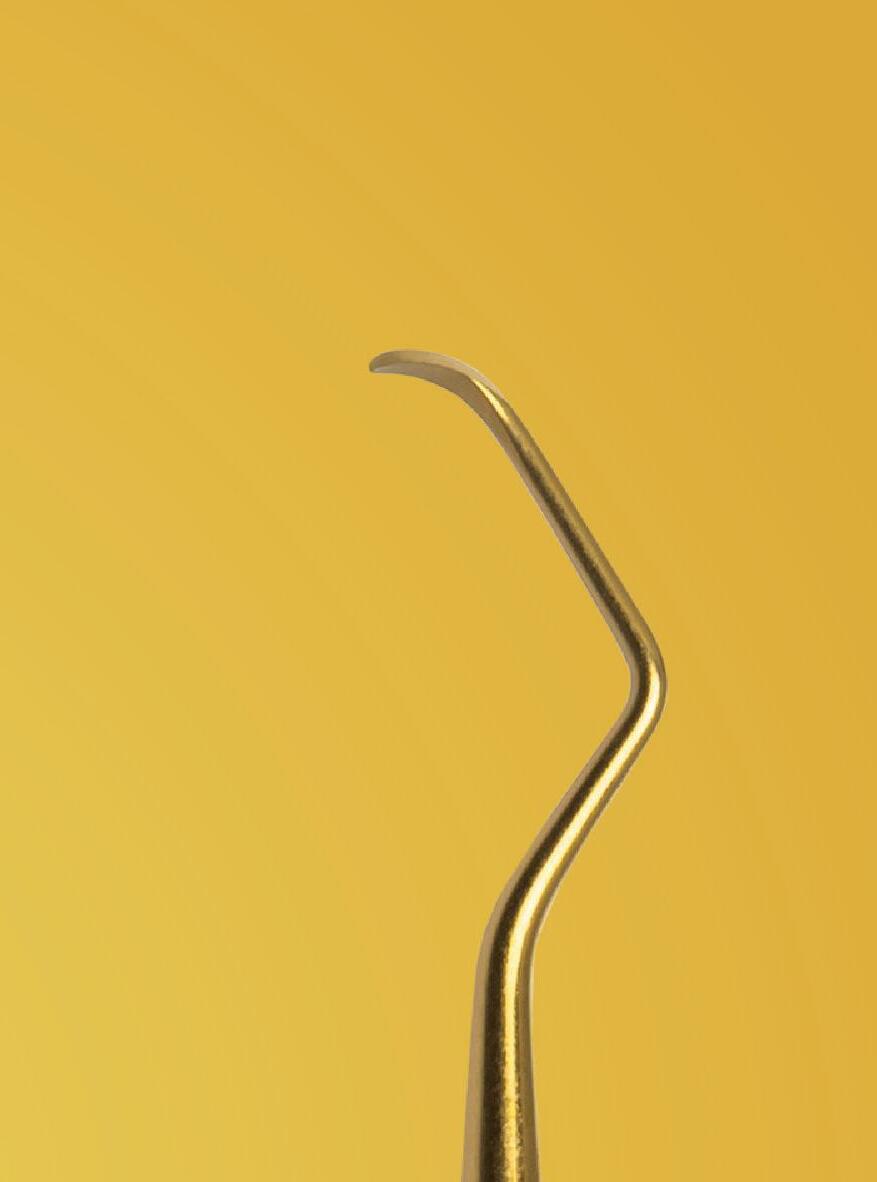

Working in perfect harmony

Synergy, as defined by the Cambridge Dictionary, is ‘the combined power of a group of things when they are working together that is greater than the total power achieved by each working separately’. When carrying out surgical procedures it is important that you use equipment solutions developed to offer a synergistic approach to your surgical processes. The equipment and instruments used should work in harmony to allow you to provide top quality treatment.

When it comes to synergy in dental implant procedures, such an approach often enables dental professionals to achieve better accuracy during the surgical phase. For instance, guided implant surgery utilises computer-generated surgical guides to enhance the precision of implant placement. By combining 3D imaging technology with specialised surgical instruments, dental clinicians are able to carefully plan the position, angle, and depth of the dental implant prior to the actual surgery. This collaborative effort between advanced imaging software and specialised instruments ensures that the implant is placed precisely in the desired location, leading to better aesthetic outcomes and increased patient satisfaction.

Seamless integration

Another advantage of instrument synergy in dental implant procedures is the reduced risk of surgical complications. Using specially designed surgical instrument and handpieces, allow dentists to ensure that they have everything necessary and readily available during a procedure. This allows the dental team to work efficiently and

effectively. The benefits of using compatible handpieces and equipment ensures that they can be seamlessly integrated into the surgical workflow, further reducing the time required for the procedure.

Seamless integration of instruments in dental implant procedures can also improve patient comfort and reduce recovery time. Advanced technology, such as piezoelectric instruments using ultrasound technology, offers precise and controlled cutting of bone, minimising trauma to the surrounding tissues. This means that patients experience less pain, swelling and bruising post-surgery, leading to a quicker and more comfortable recovery. Additionally, the combined use of specialised instruments, such as tissue punches and implant placement tools, allows for minimally invasive techniques that preserve the integrity of soft tissues. By reducing damage to the surrounding structures, patients experience less post-operative discomfort and achieve quicker healing.